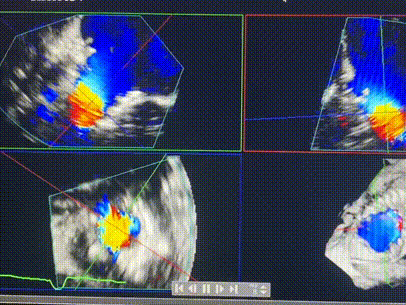

術(shù)前超聲提示重度三尖瓣反流

術(shù)后超聲顯示僅殘余微量瓣周漏